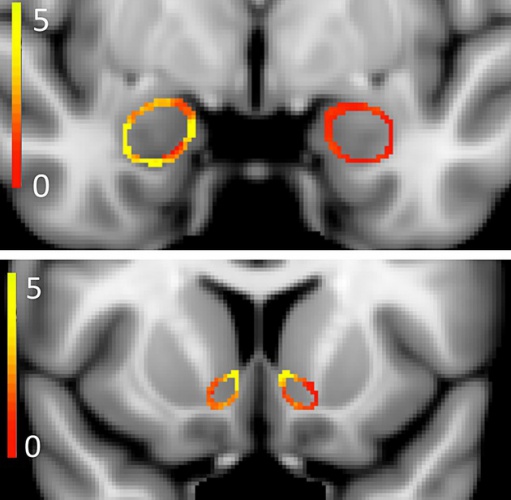

En el estudio se compararon escáneres cerebrales de fumadores de marihuana de entre 18 y 25 años. Los resultados, según los propios investigadores, fueron sorprendentes, cita el diario 'The New York Times'.

Según el rotativo, incluso en los siete participantes que fumaban solo una o dos veces a la semana se notaron diferencias estructurales en dos regiones importantes del cerebro. Cuanto más fumaban los individuos, mayores eran las diferencias, agrega.